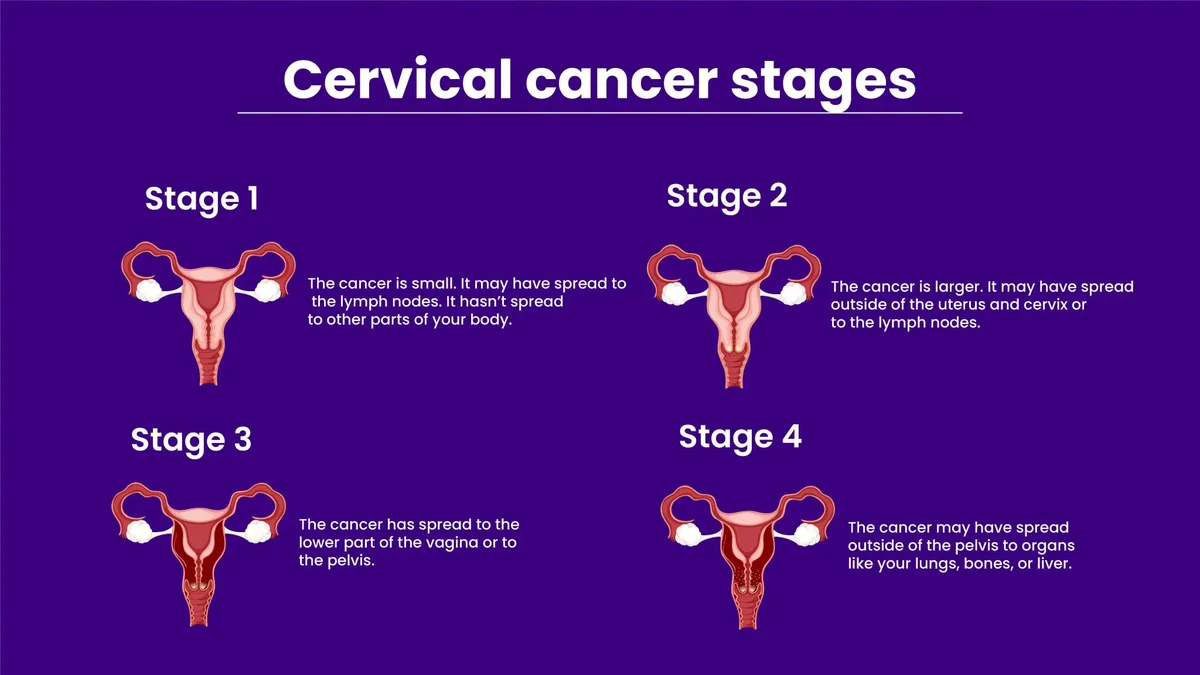

女性身体出现这8个信号,或是宫颈癌的早期征兆!

近年来,随着宣传的不断扩大,越来越多的人开始了解到 宫颈癌 与 HPV (人乳头瘤病毒)有关。确实,超过90%的宫颈癌患者是因为感染了HPV。感染了HPV,意味着患子宫颈癌的风险更高。